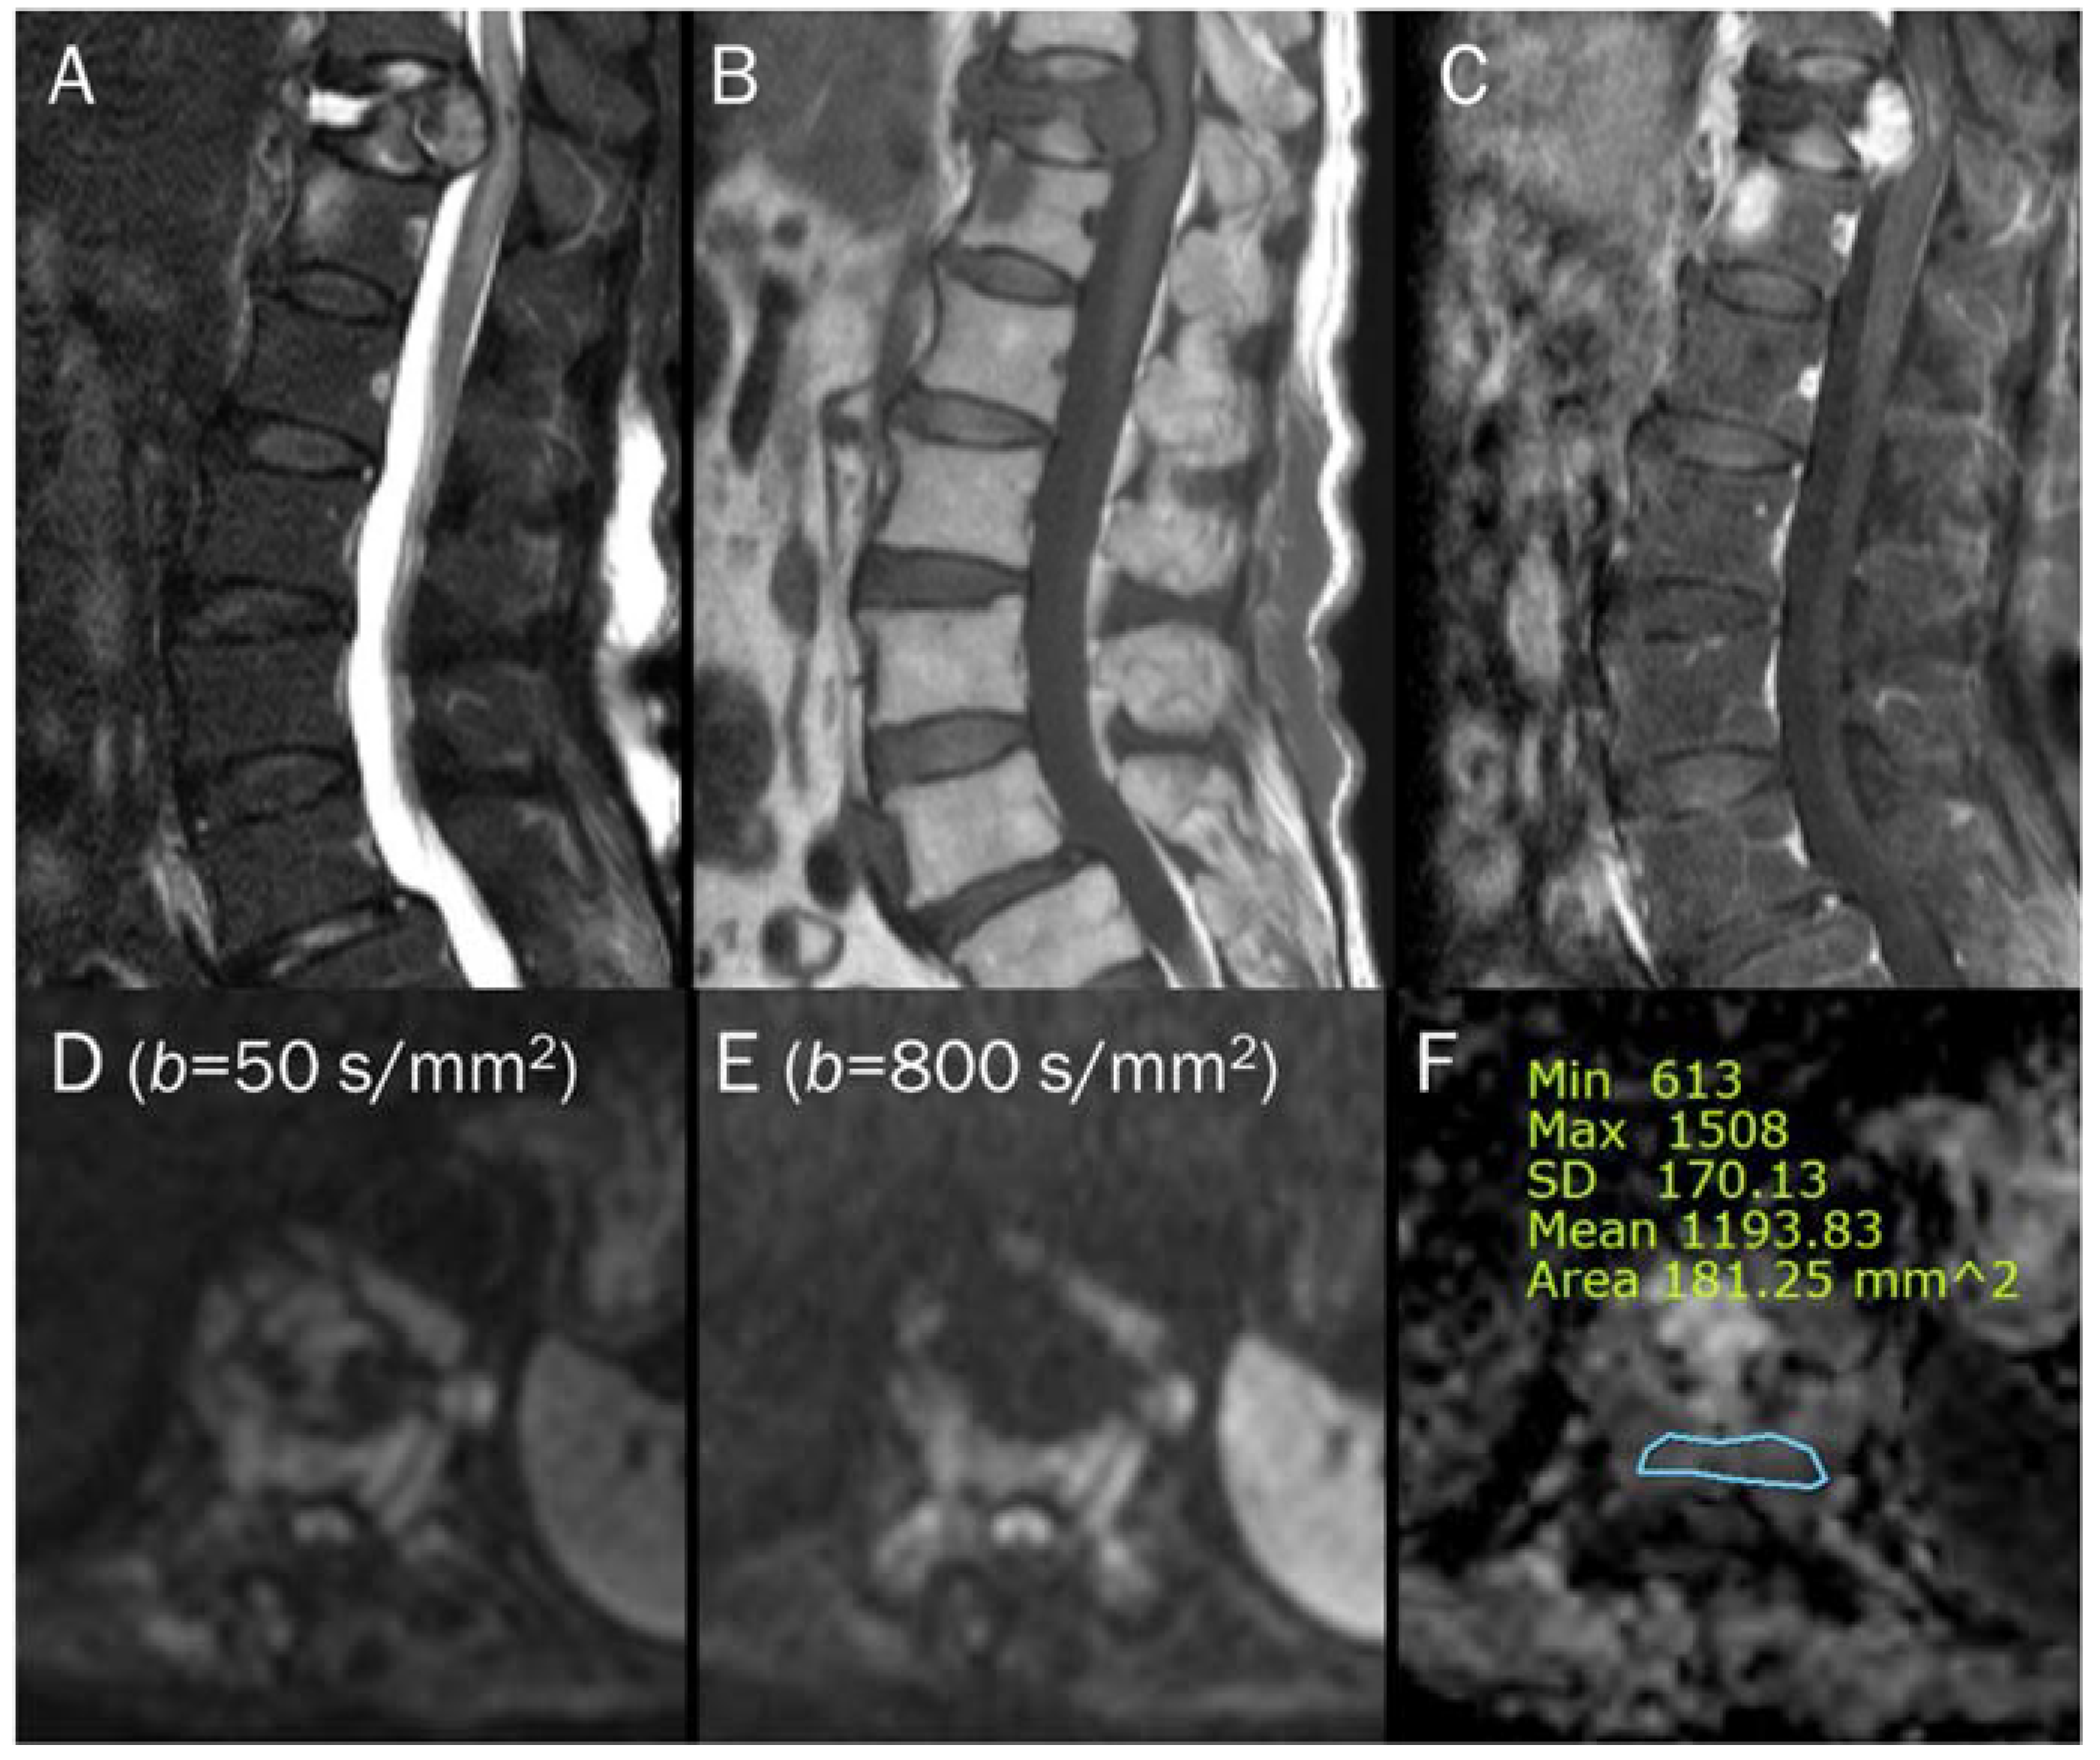

7.4. Vertebral Endplate Changes

| Modic type 1 vertebral endplate change | T2 black-out | Lipid laden cells |

- Modic, M.T.; Steinberg, P.M.; Ross, J.S.; Masaryk, T.J.; Carter, J.R. Degenerative disk disease: Assessment of changes in vertebral body marrow with MR imaging. Radiology 1988, 166, 193–199. [Google Scholar] [CrossRef]

- Braithwaite, I.; White, J.; Saifuddin, A.; Renton, P.; Taylor, B.A. Vertebral end-plate (Modic) changes on lumbar spine MRI: Correlation with pain reproduction at lumbar discography. Eur. Spine J. Off. Publ. Eur. Spine Soc. Eur. Spinal Deform. Soc. Eur. Sect. Cerv. Spine Res. Soc. 1998, 7, 363–368. [Google Scholar] [CrossRef]

- Oztekin, O.; Calli, C.; Kitis, O.; Adibelli, Z.H.; Eren, C.S.; Apaydin, M.; Zileli, M.; Yurtseven, T. Reliability of diffusion weighted MR imaging in differentiating degenerative and infectious end plate changes. Radiol. Oncol. 2010, 44, 97–102. [Google Scholar] [CrossRef]

- Patel, K.B.; Poplawski, M.M.; Pawha, P.S.; Naidich, T.P.; Tanenbaum, L.N. Diffusion-weighted MRI “claw sign” improves differentiation of infectious from degenerative modic type 1 signal changes of the spine. AJNR Am. J. Neuroradiol. 2014, 35, 1647–1652. [Google Scholar] [CrossRef]